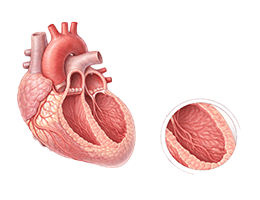

심근경색 (Myocardial Infarction)

협심증 (Angina Pectoris)

심근병증 (Cardiomyopathy)

심장판막질환 (Valvular Heart Disease)

심부전 (Heart Failure)

비대성심근병증 (Hypertrophic Cardiomyopathy)

확장성심근병증 (Dilated Cardiomyopathy)

울혈성심부전 (Congestive Heart Failure)

심근염 (Myocarditis)

심막염 (Pericarditis)

심내막염 (Endocarditis)

심정지 (Cardiac Arrest)

돌연심장사 (Sudden Cardiac Death)

심방세동 (Atrial Fibrillation)

심실빈맥 (Ventricular Tachycardia)

심실세동 (Ventricular Fibrillation)

서맥 (Bradycardia)

심장판막질환 (Heart Valve Disease)

폐동맥고혈압 (Pulmonary Hypertension)

심장병성쇼크 (Cardiogenic Shock)

심장막압전 (Cardiac Tamponade)

확장형심근병증 (Dilated cardiomyopathy)

비후성심근병증 (Hypertrophic cardiomyopathy)

제한성심근병증 (Restrictive cardiomyopathy)

감염성심내막염 (Infective endocarditis)